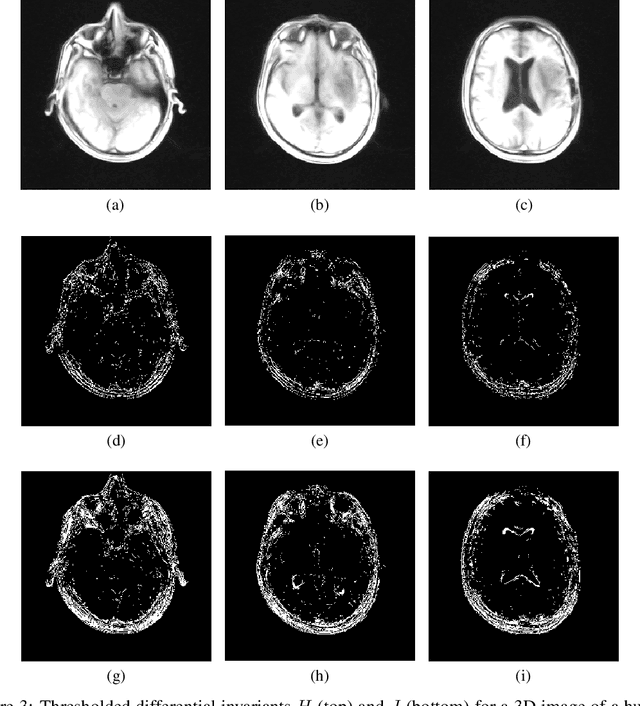

Abstract:Image feature points are detected as pixels which locally maximize a detector function, two commonly used examples of which are the (Euclidean) image gradient and the Harris-Stephens corner detector. A major limitation of these feature detectors are that they are only Euclidean-invariant. In this work we demonstrate the application of a 2D affine-invariant image feature point detector based on differential invariants as derived through the equivariant method of moving frames. The fundamental equi-affine differential invariants for 3D image volumes are also computed.